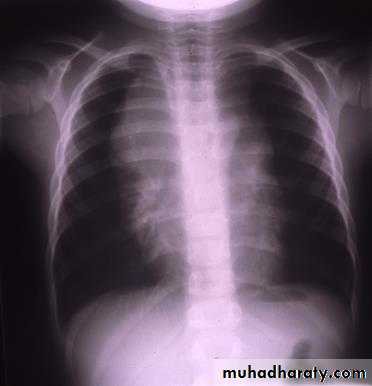

Before Rx.After Rx.